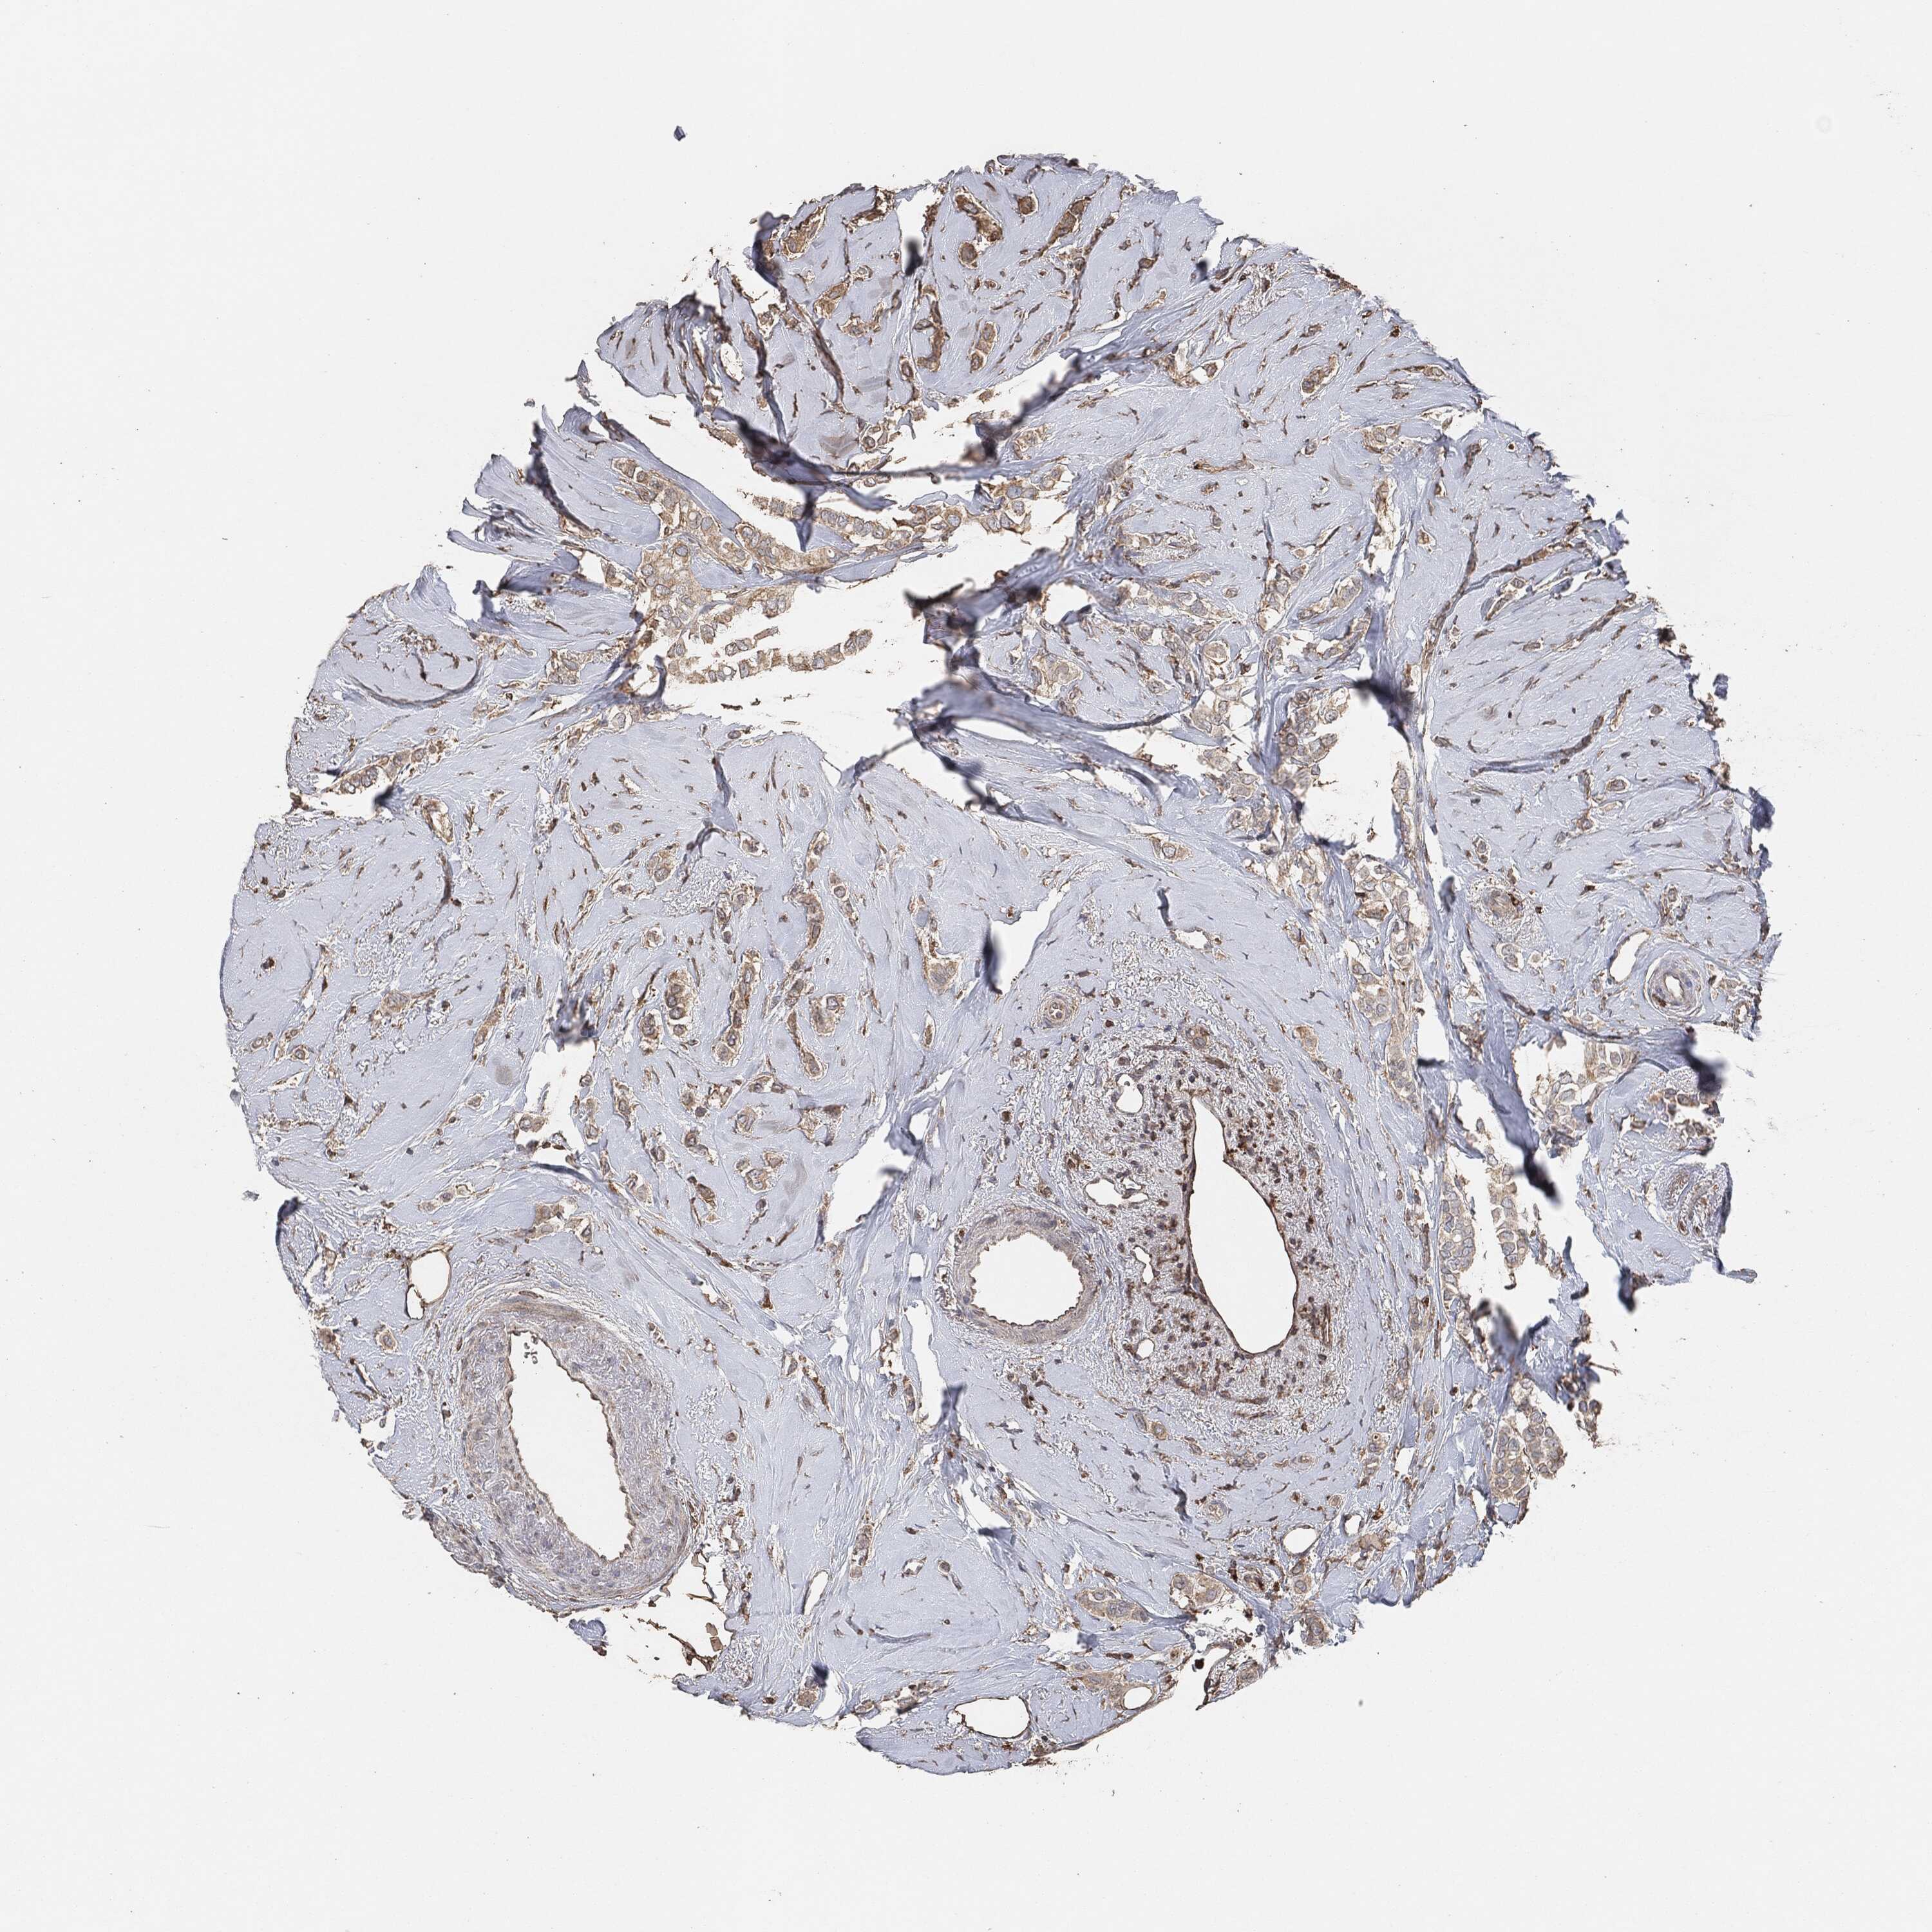

CANCER BREAST CANCER Show tissue menu

BRCA TCGA BRCA VALIDATION PROTEIN EXPRESSION